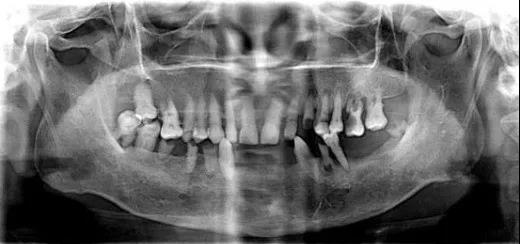

相较于传统的二维X光影像,通过Sirona CBCT重建后我们可以得到三维口内图像。

它的出现彻底改变了传统口腔颌面放射学设备仅能提供二维图像的历史,可以三维显示病变结构,大大提高了诊断能力。

▲ 常见的牙片是二维的

种植医生可以从任意角度观察分析病例,如缺牙区牙槽骨吸收程度、余留牙是否有炎症等需要先进行治疗以避免干扰种植手术的问题。

马先生的牙齿情况